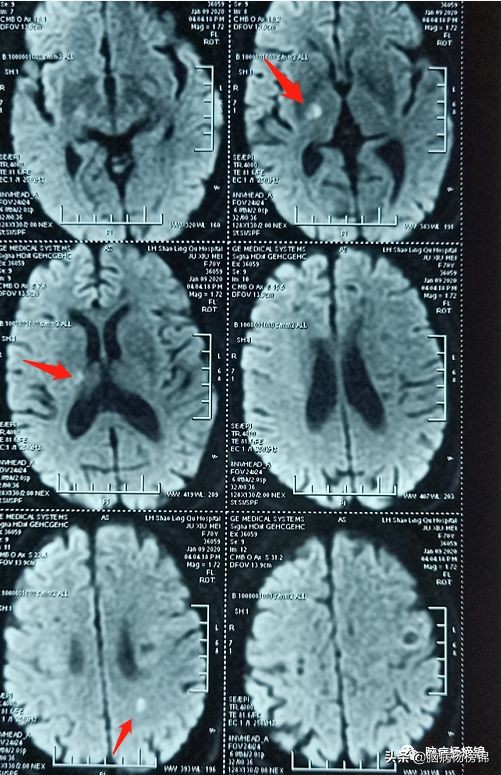

DWI显示:急性脑梗塞。